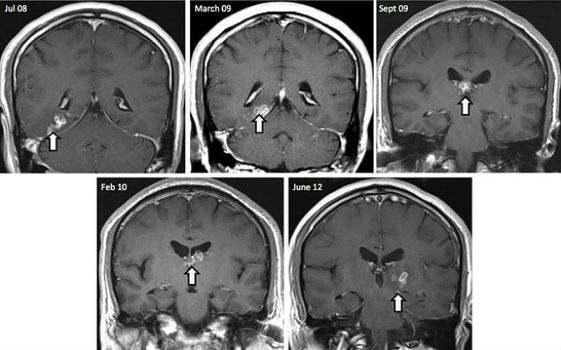

Doctors Discover Parasitic Tapeworm Living In Man’s Brain For Four Years

A man had a parasitic tapeworm living in his brain for four years before doctors knew it was there, according to a new report published in the journal Genome Biology.

The 50 year old first visited doctors in 2008, with complaints of headaches, seizures, memory loss and a change in his sense of smell.

Following an MRI scan, which showed up what appeared as a cluster of lesions in his brain, specialists began taking biopsies and tested the man for a number of diseases including HIV, lime disease and syphillus.

Doctors continued to monitor the condition over four years, but were amazed to find the remains of 10 cm ribbon-shaped larval worm amongst the brain tissue.